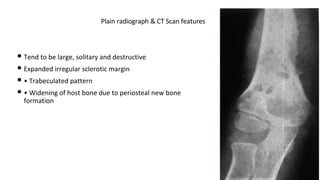

• Tend to be large, solitary and destructive

• Expanded irregular sclerotic margin

• • Trabeculated pattern

• • Widening of host bone due to periosteal new bone

formation

Plain radiograph & CT Scan features